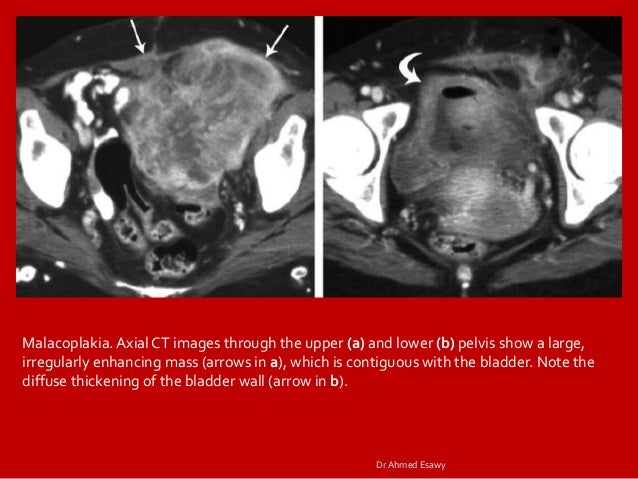

Imaging Cystitis Dr Ahmed Esawy